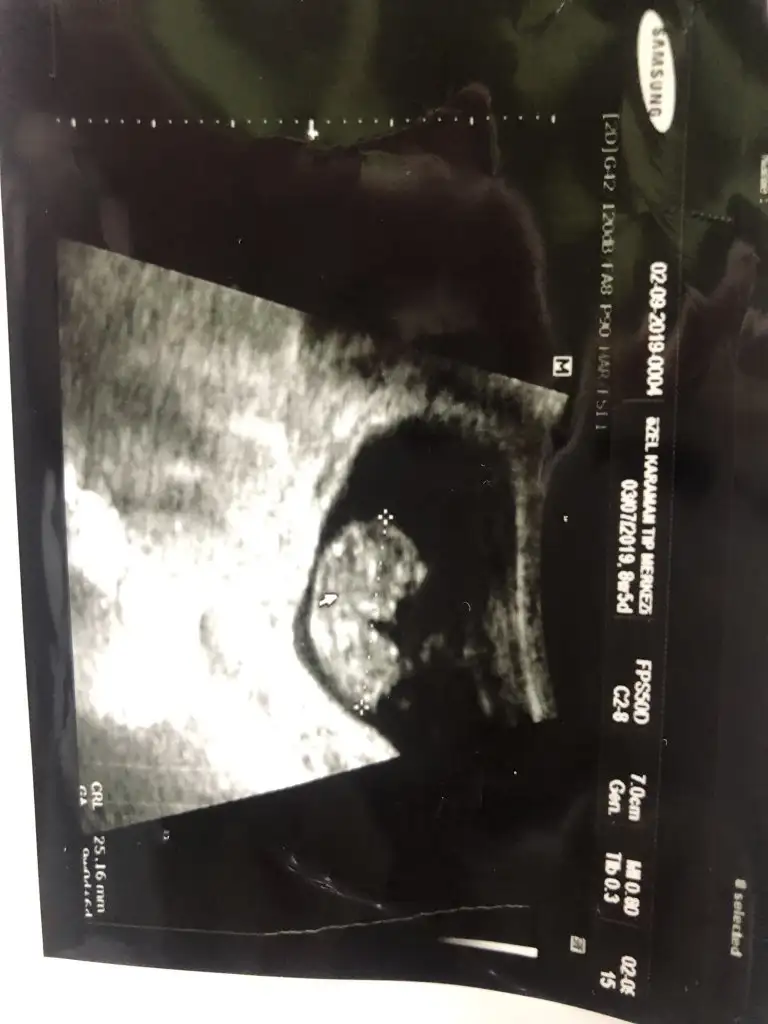

Sag tarafa yakın kız siz 11 yada 12 hafta nub teorisine paylaşın

Erkeğe benzettim bendeKızlar merhaba 10 haftalık doktor kıza benzetti sizce ne yorum yaparsanız seviniriö![]()

Twiekkürler canım yprumun için neye bakarak erkek dedin acaba kafa yapısı nub falan mı ben hiç yorumlayamıyorum da ondan sordumErkeğe benzettim bende![]()